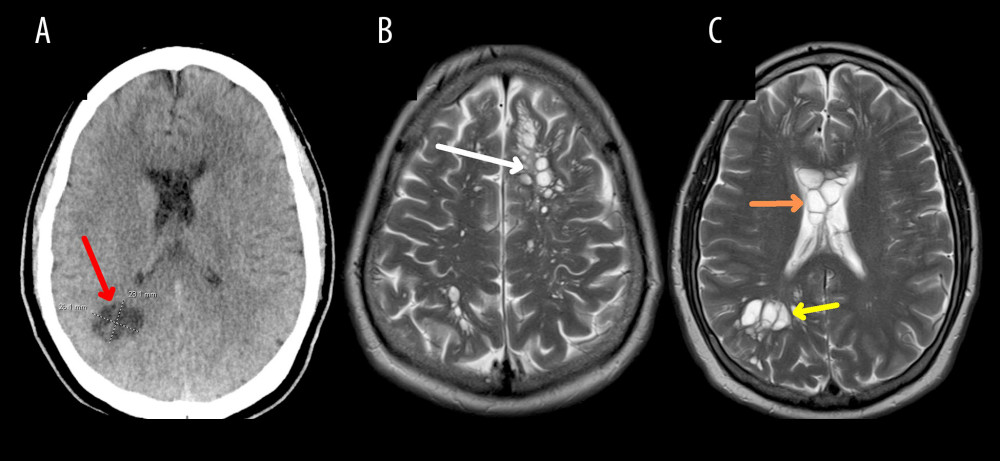

Los médicos especularon que las intensas migrañas, que no respondían a los medicamentos convencionales, podrían estar relacionadas con el consumo de tocino crudo por parte del paciente. Tras realizar una tomografía, se detectaron múltiples quistes en todo el cerebro, lo que llevó al ingreso del paciente a un hospital en Orlando para exámenes más detallados.

Los análisis revelaron que los quistes eran larvas de tenia parasitaria, causando una infección conocida como neurocisticercosis. Esta infección se produce cuando una persona ingiere huevos de tenia procedentes de las heces de un individuo con tenia intestinal.

El tratamiento incluyó esteroides y agentes antiparasitarios, lo que ayudó a aliviar los síntomas del paciente y reducir los quistes cerebrales. Este caso subraya la importancia de la preparación adecuada de los alimentos y la higiene personal para prevenir enfermedades parasitarias.